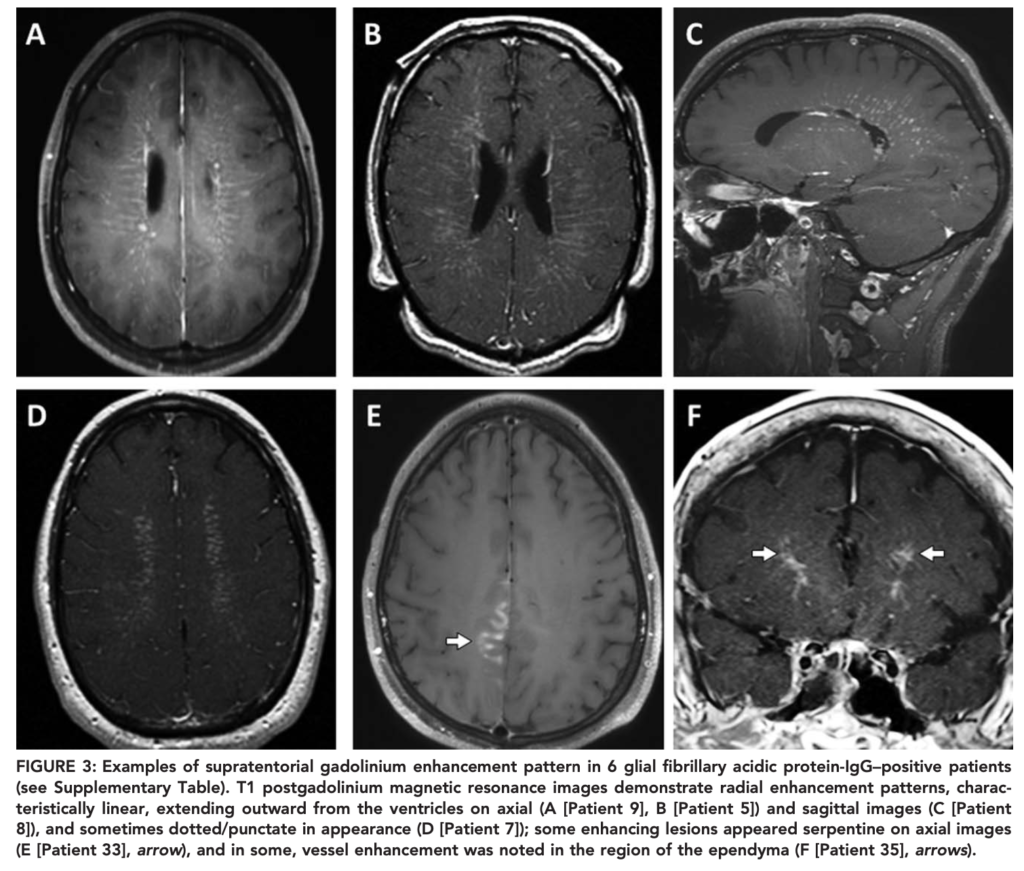

ガドリニウムによる造影所見68%

線状脳室周囲放射状ガドリニウム増強(LPRGE; linear periventricular radial gadolinium enhancement)パターンが約半数に認められる。

*LPRGEはリンパ腫様肉芽腫症・神経サルコイドーシス・中枢神経系血管炎の患者でも報告されている。